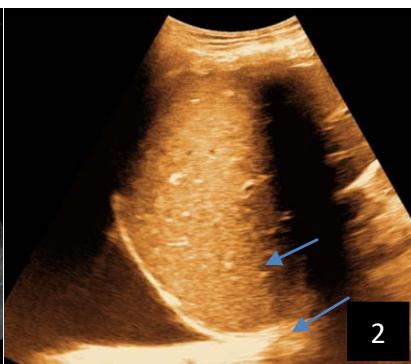

Iconography 1: 54-year-old patient with an intra-splenicsolid mass, anatomopathologically compatible with lymphoma: images 1 and 2: right pleurisy of moderateabundance, image3: celiacadenopathy, image 4: free ascites of moderateabundance, images 5 and 6: intra-splenicsolid mass of around $1418.16\mathrm{ml}$ in B mode and elastographyshowing areas of tumourrigidity, images 7-10: oblique linear images, showingbiopsy gun tracks.